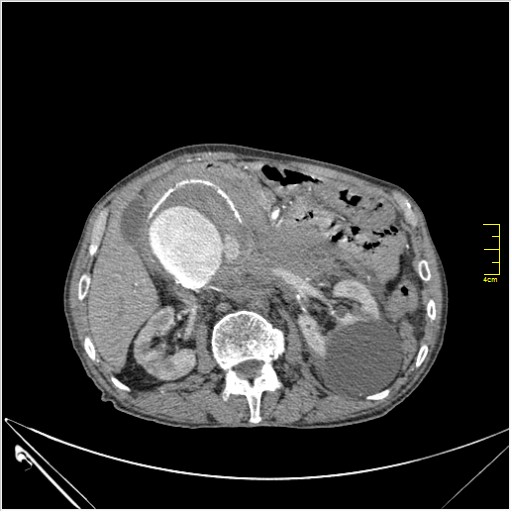

КТ брюшной полости. Мужчина с пальпируемой опухолью в животе

Пациент Т. 64 года, обратился на КТ брюшной полости амбулаторно (!), по направлению семейного врача с диагнозом abdominal mass, буквально: образование брюшной полости.